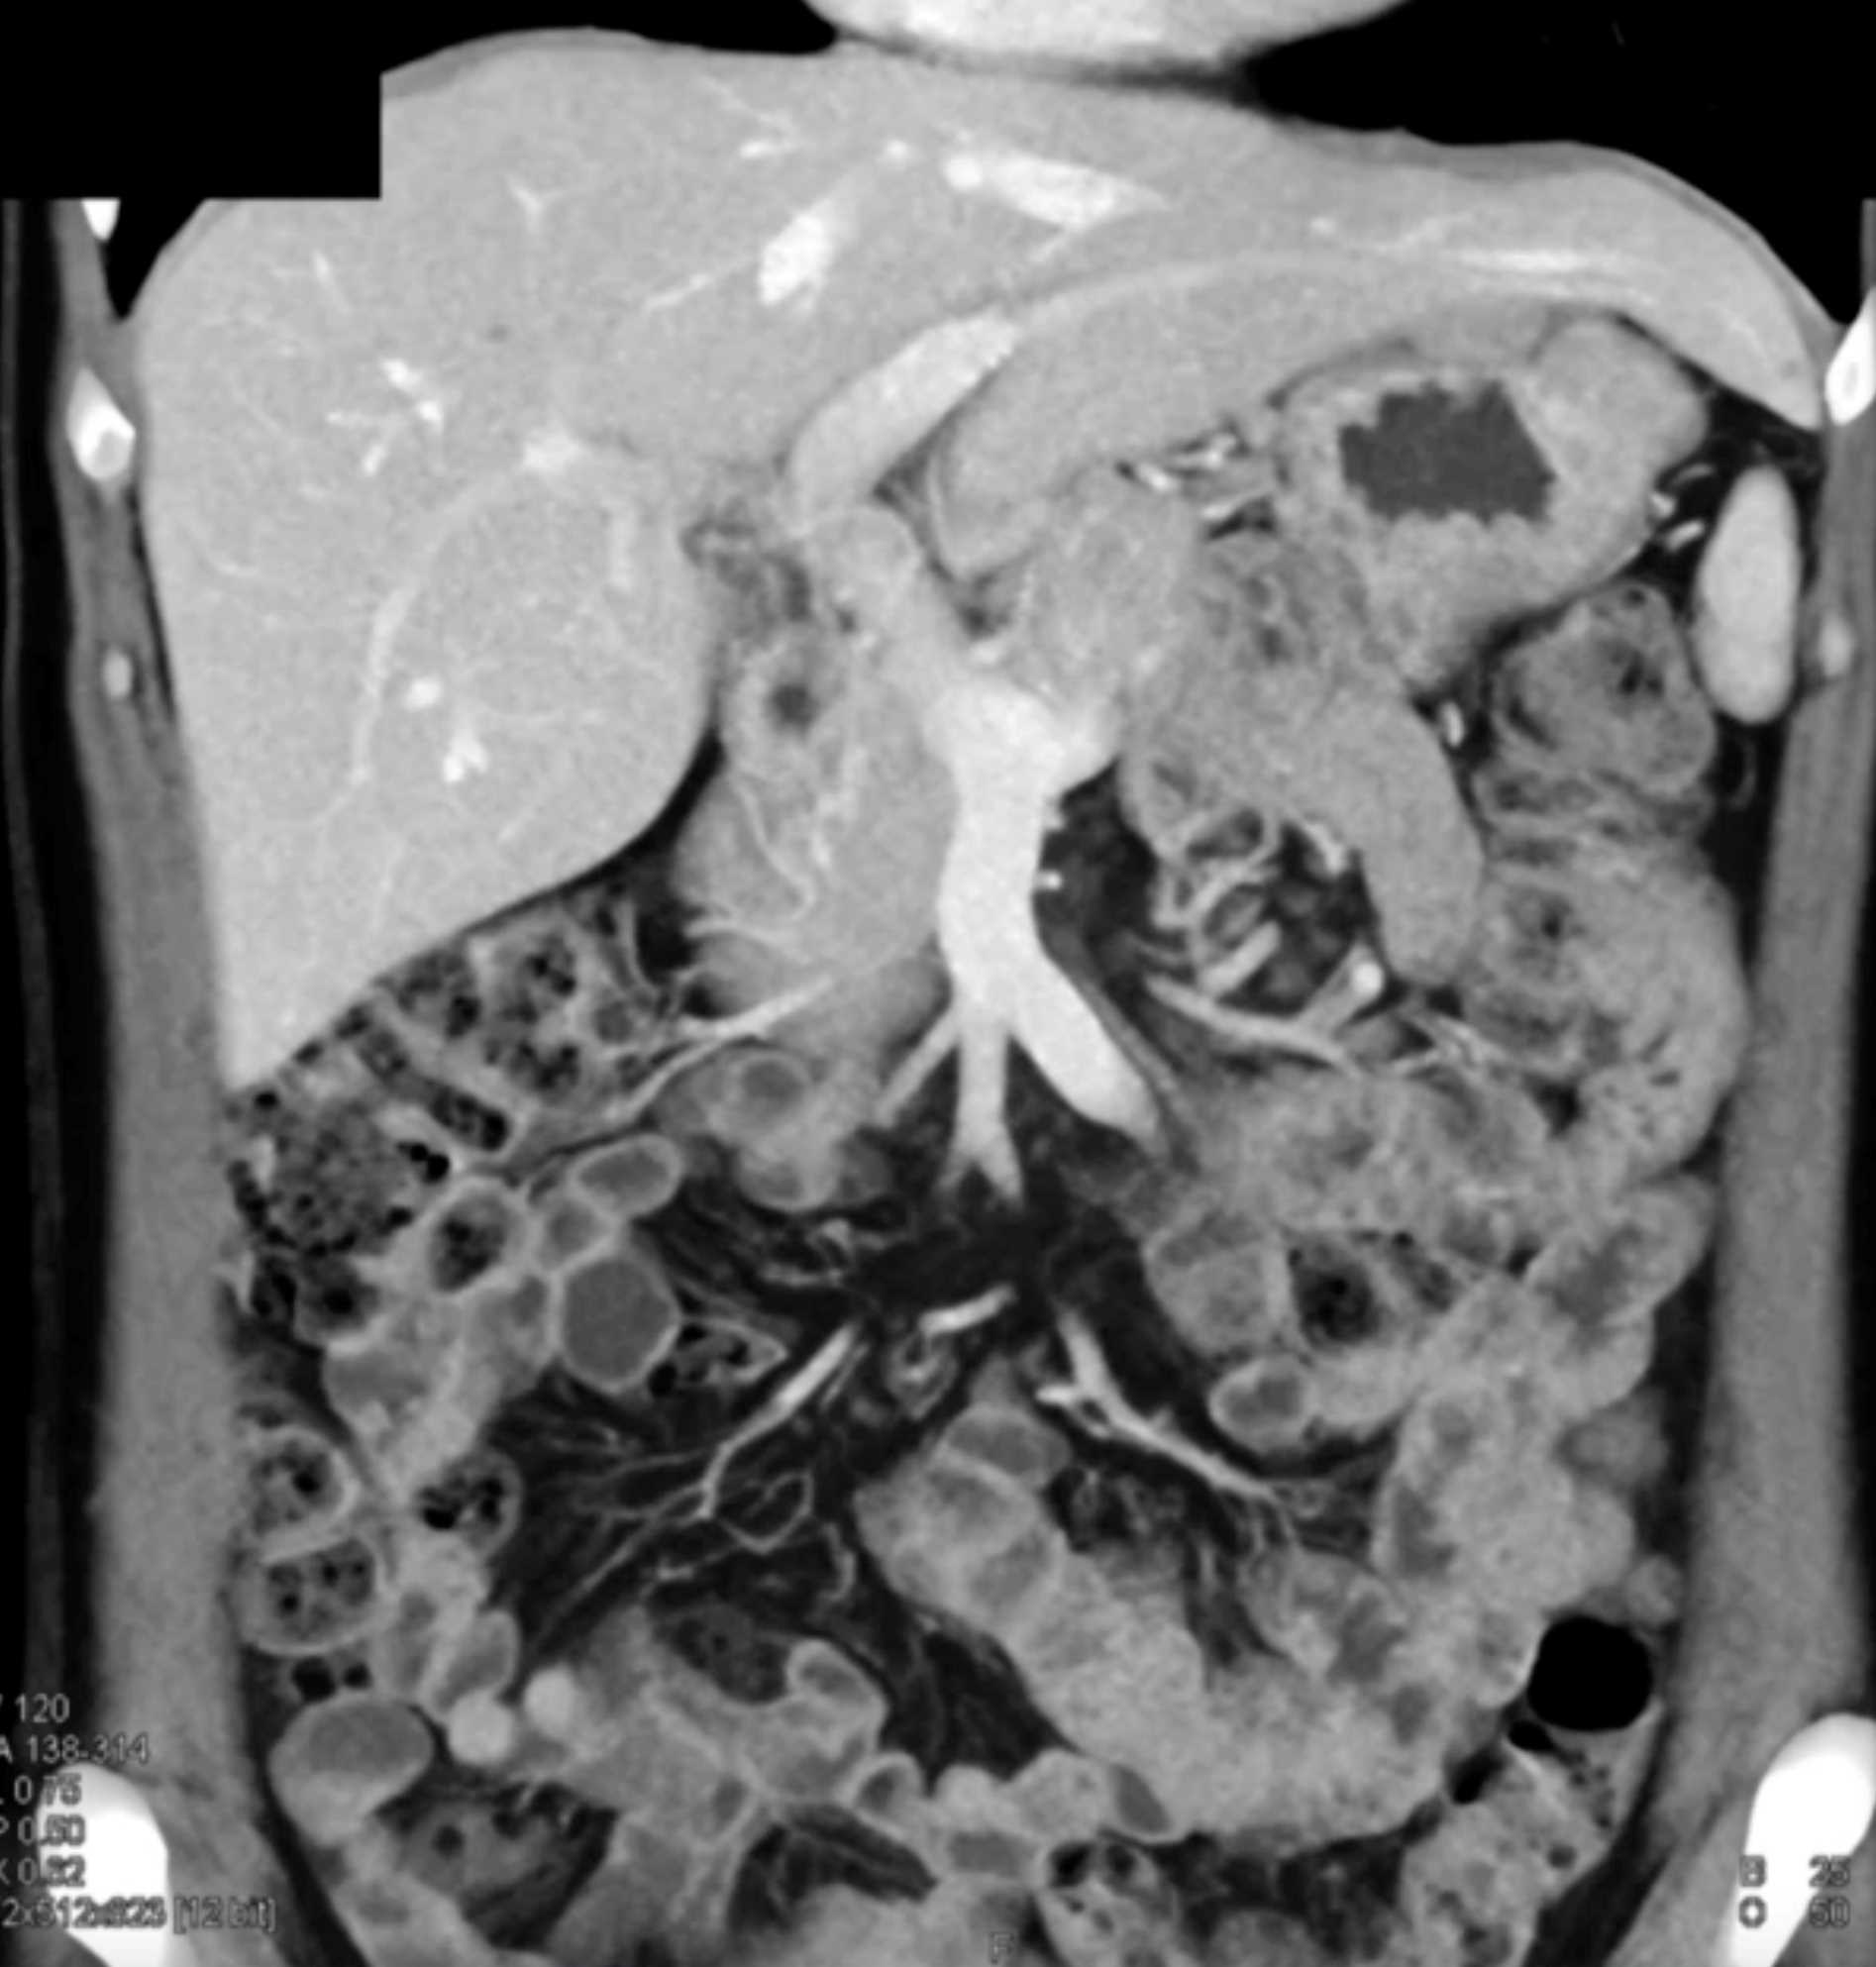

Multiple Gastric GIST Tumors with Spread to Nodes (Carney-Stratakis Syndrome)